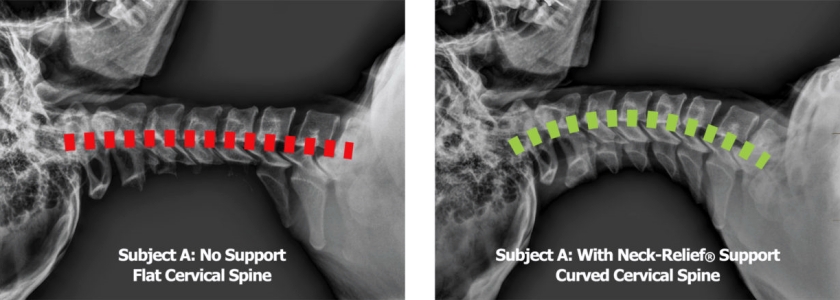

머리와 목 자세(head & neck posture)에 좋은 편한 베개(comfortable pillow)의 조건은, 우리가 바로 누웠을 때(supine) 변곡점(inflection point)들을 지지(supporting)할 수 있는 베개(pillow)입니다. 그러니까 후두골(occipital bone)과 목뼈(cervical) 1번, 목뼈(cervical) 7번과 등뼈(thoracic) 1번입니다. 해당 영역(area)들은 서로 다른 성격이 뚜렷하게 내재된 골격(skeleton)들의 경계선(boundary line)입니다. 이 지점(area)에서의 부정한 골격(skeleton)의 위치(position)와 자세(posture)는 서로 다른 뼈(bone)들에 대해 잘못된 위치(faulty position)로 전이된 상태(transferred condition)에서 수면(sleep)을 취하게 될 수 있습니다.

경추(cervical)는 기본적으로 전방(anterior)으로 경사진 만곡(inclined curve)의 형태(shape)를 지닙니다. 이때 가장 많은 만곡도(curved degree)는 보편적으로 목(neck)의 중간 영역(center area), 혹은 중간(center)에서 약간 하부 영역(inferior area)에 치우쳐져 있습니다. 그러니까 이러한 영역(area)을 떠받칠 수 있는 베개(pillow)가 좋습니다.

다만 중요한 것은 사람마다 척추 자세(spinal posture)와 목 상태(neck condition) 등에 따라, 현재 형성되어있는 목(neck의 만곡도(curved degree)가 다른 만큼, 개인차를 고려하여 만곡도(curved degree)에 적절히 충족될 수 있는 만큼의 지지도(supporting degree)가 필요합니다. 그러니까 예를 들어 과전만 형태(hyperlordosis shape)의 사람이라면 그만큼 전방(anterior)으로 치우진 만곡도(curved degree)가 증가되어있으니, 해당 영역(area)을 더 크게 보충(supplement)시키기 위해 목(neck)의 중하단 영역(middle & inferior area)을 지면(ground)으로부터 채워줄 수 있는 베개(pillow)가 필요할 것입니다. 반면, 정상 만곡(normal curve)에서 반대로 벗어난 일자목(straight neck)의 형태(shape)나 역C자 형태(inverse C shape)의 목(neck)은 오히려 우리에게 하여금 경추베개(cervical pillow)라고 하는 것들이 현재 상태(condition)에서는 좋지 않을 수 있습니다. 이런 대상자들은 오히려 바로 누운 자세(supine posture)에서도 정상적인 만곡도(curved degree)로 어느 정도조차 회복(recovery)되는 형태(shape)로 자세(posture)가 잡혀 지지 않는다면, 지면(ground)과의 거리(distance)만큼만 보충(supplement)될 수 있도록 목(neck)을 받쳐주면 됩니다. 일부러 처음부터 정상 만곡도(normal curved degree)를 만들 수 있는 베개(pillow)를 선택(choice)하는 것이 아닌, 비교적 비정상적인 베개(abnormal pillow)의 선택(choice)으로 보일지라도 해당 대상자에게는 일자목(straight neck)이나 역C자 형태(inverse C shape)를 존중하는 베개(pillow)가 실제 대상자에게는 더욱 편한 베개(comfortable pillow)가 됩니다.